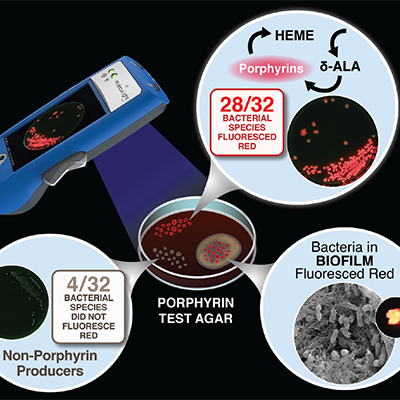

In vitro detection of porphyrin-producing wound bacteria with real-time fluorescence imaging

Jones, LM et al. Future Microbiol 2020